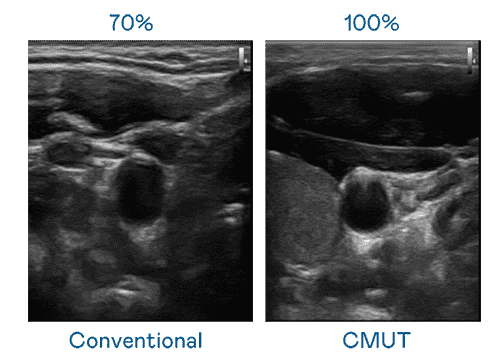

CMUT 技术是一种用电容式微机电元件来产生超音波讯号的技术。。。。与传统 PZT 压电式技术相比,,,CMUT 频宽增加 30%,,更宽频的超音波讯号让影像解析度大幅提升,,,是实现高影像品质医疗超音波扫描、、、促进精准医疗发展的关键技术。。

大频宽带来超清晰影像

超音波影像的解析度高低,,,,首先取决于探头能发出的讯号频宽。。。。z6mg·人生就是博 CMUT 可提供高清晰的超音波讯号,,,提供高频宽、、高灵敏度、、影像纹理细节更高的超音波影像,,,协助医护人员缩短影像判读时间及利用精准的医疗影像进行诊断。。。